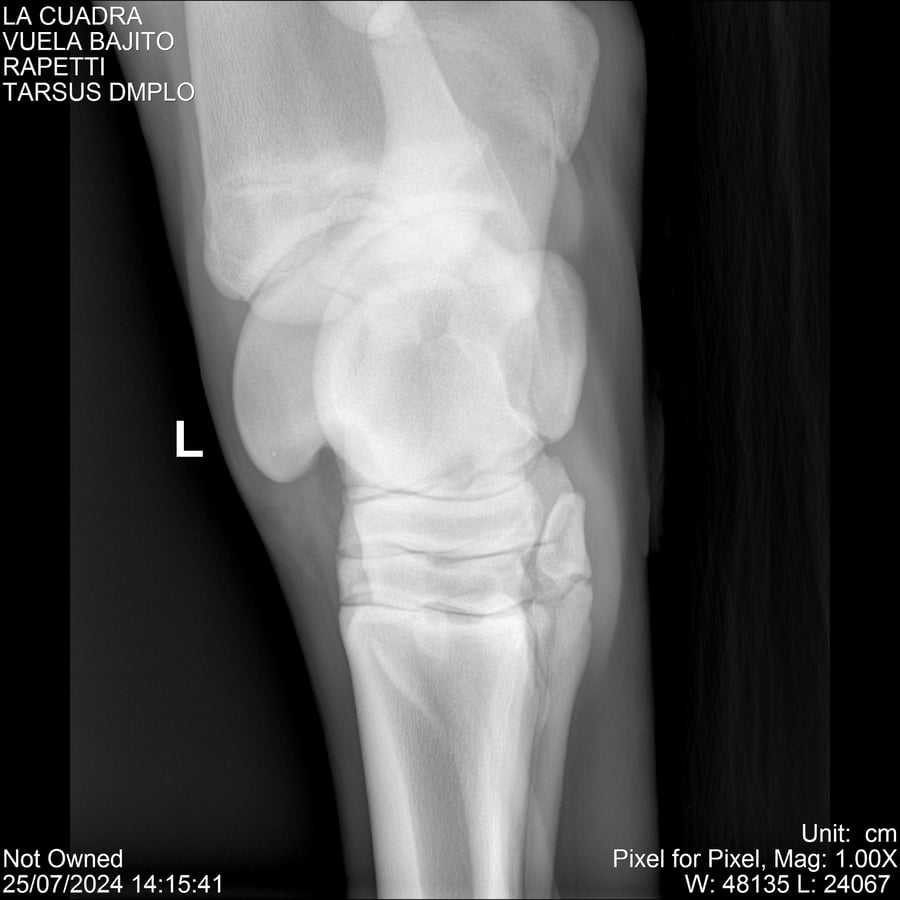

LOTE 16, VUELA BAJITO Lote Anterior Volver al remate Lote Siguiente Ficha Contacto Montevideo - Ficha del Lote Identificador: #284451 Categoría: Yeguarizos Montevideo - 77 Visualizaciones ClicData Contacto Empresa: Abelenda N. R., Walter Hugo Nombre*: Teléfono* : E-mail* : Mensaje Enviar Registrese gratis Este contenido Exclusivo está disponible sólo para usuarios registrados Ingresar